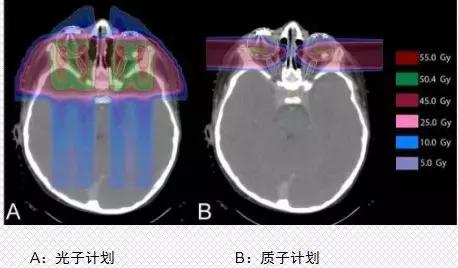

第二大优势是质子的辐射可以最大限度降低对正常组织的伤害,对目标肿瘤细胞造成最大的损害。以儿童髓母细胞瘤为例,我们可以看到普通放疗产生的大部分副作用,质子都完美的规避了。

第三大优势是质子治疗可以降低二次肿瘤的发病率。以头颈肿瘤为例,常规放疗比质子治疗的辐射剂量高出25Gy,这意味什么呢?25Gy=你做了12500头颈CT,增加96%罹患二次肿瘤的风险!